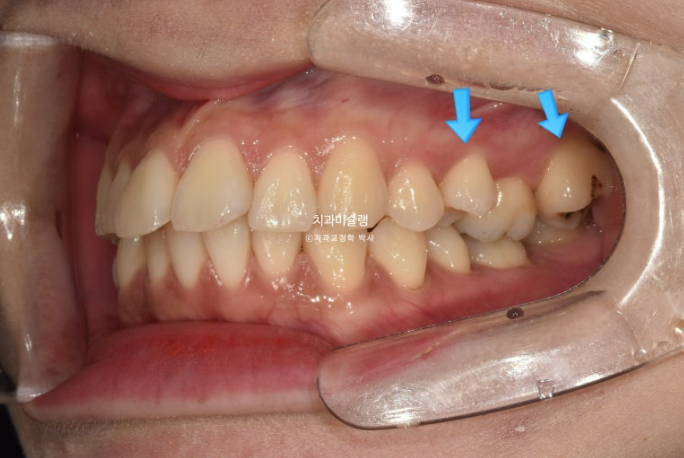

좌측에는 가위교합이 소구치에 하나 대구치에 하나 총 2군데 있습니다.

교합을 담당하는 어금니 중 절반이 가위교합 상태이니, 좌측으로 씹기가 힘든 상태입니다.

아래 큰어금니는 안으로 쓰러져 있습니다.

중심선 불일치가 아직 조금 남았고, 가위교합은 모두 해소가 되었습니다.